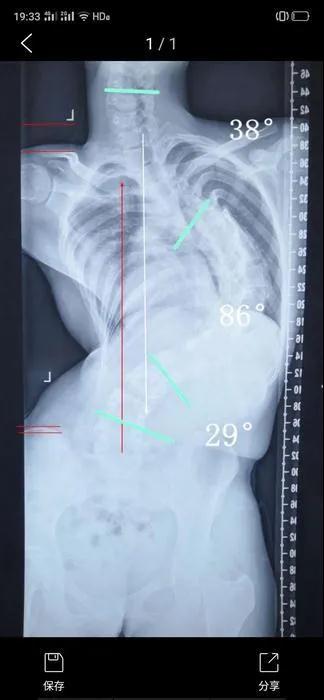

矫形前影像学图。(受访者供图)

由于小雅的侧弯角度比较大,达到了85,又处在青春发育时期,若是侧弯角度进一步加重,就可能会影响到心肺等功能,因此,当务之急需要接受矫形手术。